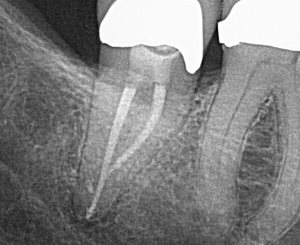

#31 with 2 canals can feel exciting because, as a provider, we imagine it being a “quick” case! We aim for increased patient satisfaction and clinical efficiency. But is a case like this

actually simple and straight-forward?

The apices of mandibular 2nd molars are often in close proximity to the mandibular canal, which houses the inferior alveolar nerve. The

EndoPilot with built-in electronic apex locator was helpful in ensuring that I instrumented this case to the exact working length. As a clinician, I feel this may help lower the risk of post-operative paresthesia.